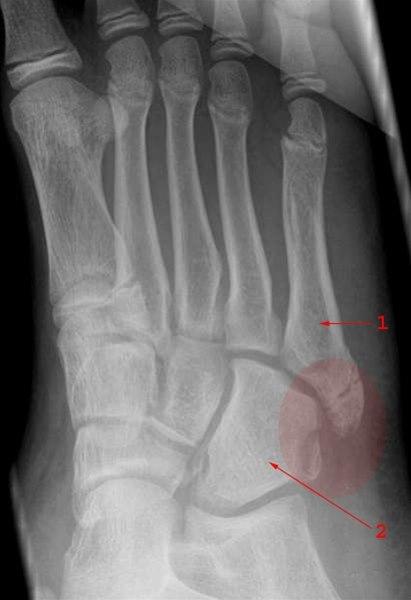

Fraktur uten feilstilling gjennom basis av femte metatars og lateralt i os cuboideum

- 5. metatars

- Os cuboideum (terningbenet)